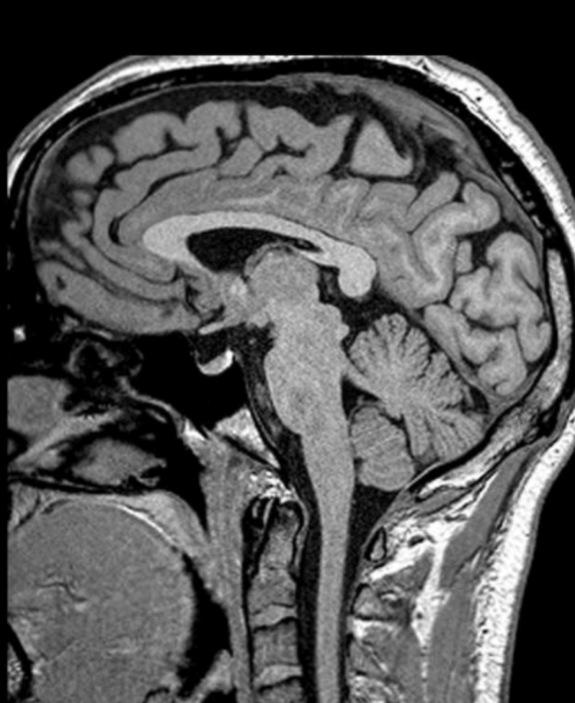

Schnittbildanatomie -MSwoboda